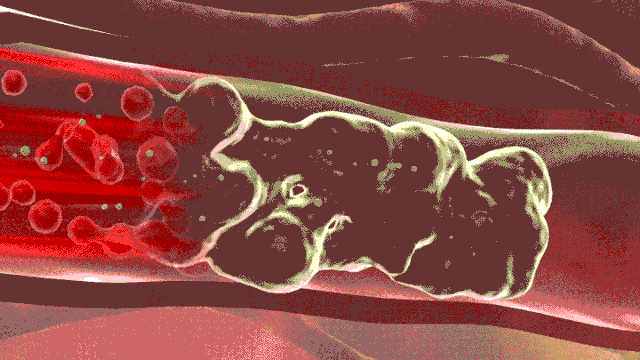

動脈瘤并非腫瘤,而是動脈壁發(fā)生擴張、向外膨出的囊性物體。王主任把腹主動脈比作一條自行車胎,長期的高壓和老化,導致車胎變硬,最后形成車胎的“鼓包”,這個“鼓包”就是腹主動脈瘤。主動脈是身體的主干血管,承受直接來自心臟跳動的壓力,血流量巨大,出現腹主動脈瘤,如果不進行恰當和及時的治療,后果嚴重。其中最大的風險為瘤體破裂、大出血、死亡,此外,腹主動脈瘤形成后,局部血流形成渦流,瘤腔內容易形成大量附壁血栓,血栓附于動脈瘤腔內壁,并不牢固,隨時可能脫落,造成下肢動脈栓塞、肢體嚴重缺血,治療不及時可能導致下肢壞死和截肢。